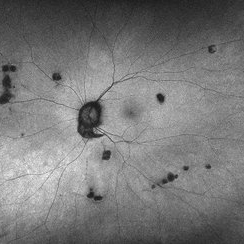

Histoplasmosis Capsulatum Retinitis OS

Histoplasmosis Capsulatum Retinitis OS

Dec 20 2021 by Brad Lovelace

Autofluorescence image of a 63-year-old woman with presumed ocular histoplasmosis syndrome OS observed for change.

Photographer: Cathy Harsma, COA

Imaging device: Optos Ultra-Widefield

Condition/keywords: histoplasmosis, presumed ocular histoplasmosis syndrome (POHS)